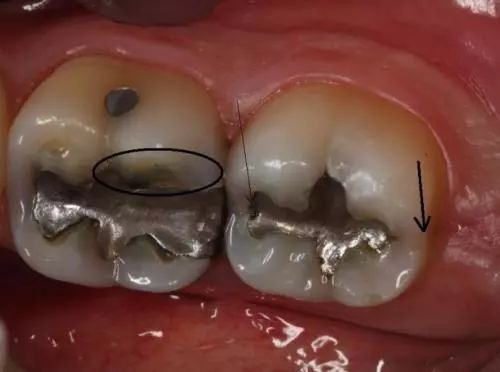

2.牙隐裂——*毒冰**会使服用者感到焦虑、亢奋或紧张,从而导致磨牙。你能看到他们的牙齿上有明显的磨耗痕迹。偶尔候就算是吃一些很软的食物(如土豆泥),也会使服用者的牙齿出现隐裂。

3.龋齿——*毒冰**成瘾者会因为口干反应而渴望吃含糖量高的食物和饮品。这样,口腔内靠糖类为生的细菌会大量繁殖,并分泌酸性物质,使牙齿损坏更严重。*毒冰**服用者的龋齿通常会从牙龈边缘发展到整个牙齿,前牙首当其冲。

4.牙周病——*毒冰**成瘾者通常不会定期做口腔检查,口腔保健的缺乏会引发牙周病。同时,牙齿和牙龈都需要血液来保持健康,*毒冰**使口腔组织的血管收缩,血流量减少,最终导致口腔组织坏死。

1.吸毒者龋齿发展到牙龈边缘以下。

2.吸毒者牙齿出现缺失。